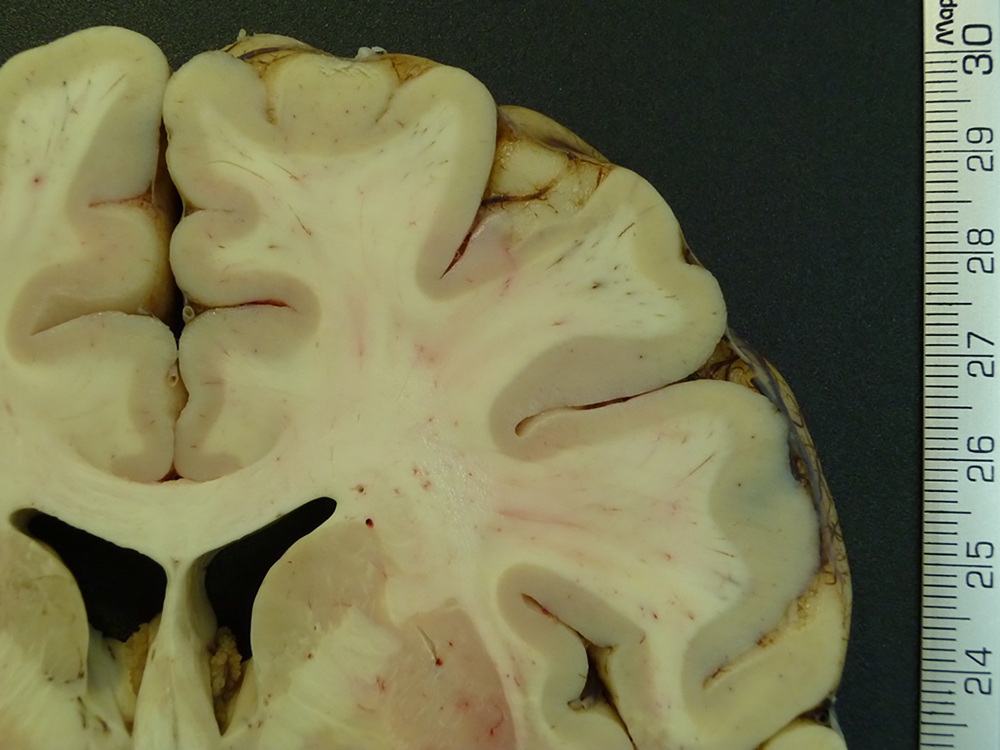

Una revisión sistemática reciente reveló que la gran mayoría de los estudios acerca de la obesidad y el cerebro reportan anomalías estructurales del cerebro de las personas con obesidad y sobrepeso (Herrmann, Tesar, Beier, Berg, & Warrings, 2019). Esta publicación develó en específico que, por medio del análisis de las imágenes por resonancia magnética, hay una consistente reducción del volumen de materia gris o corteza cerebral (esto es, el volumen que ocupan los cuerpos de las células cerebrales llamadas neuronas) de varias regiones, particularmente de las regiones frontales (la parte anterior) que se sabe están dedicadas al control de las respuestas; esto es, a la inhibición de la conducta no deseada (figura 2).

Hay evidencia también de una reducción global de la materia blanca (las fibras nerviosas de los cuerpos celulares y la red de conexiones entre neuronas) en personas con obesidad o sobrepeso. Incluso puede haber deformaciones de las fibras de conexión que enlazan entre regiones cerebrales, por ejemplo, las estructuras límbicas con las regiones prefrontales (Kullmann et al., 2016). Las estructuras límbicas son parte del cerebro involucradas en las emociones y las prefrontales en el control de la conducta; esta falla estructural de las fibras por la obesidad puede explicar el mayor riesgo de deterioro cognitivo y demencia (problemas en memoria, planeación, atención y control de la conducta) en los adultos de mediana edad y mayores con obesidad (Beydoun, Beydoun, & Wang, 2008; Gunstad, Lhotsky, Wendell, Ferrucci, & Zonderman, 2010; Tang et al., 2021).

En el caso de los niños con obesidad también hay una reducción significativa del volumen de la corteza cerebral (Ou, Andres, Pivik, Cleves, & Badger, 2015). La obesidad infantil se ha asociado con una menor densidad de neuronas en las regiones cerebrales del sistema de recompensa.